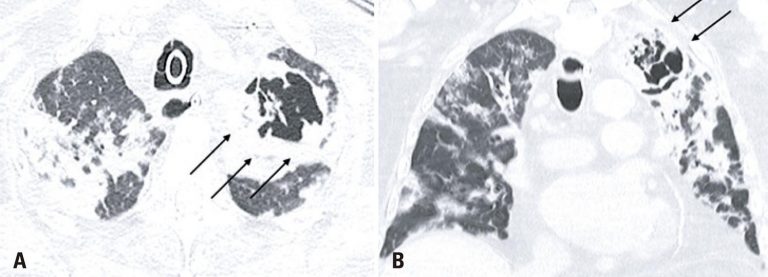

An 86-years-old male patient was admitted to the emergency department with a 1-day history of fever, dyspnea, and cough. After an assessment, there were no criteria that justified the patient’s hospitalization, therefore, he was dismissed and instructed to continue treatment at home. One week after the onset of symptoms, the patient returned with worsening dyspnea and persistent fever, which prompted his hospitalization. A chest computed tomography (CT) demonstrated typical coronavirus disease (COVID-19) findings(,) (), and the real-time polymerase chain reaction (rt-PCR) test confirmed the diagnosis. After 13 days of hospitalization, the patient experienced clinical worsening, and nosocomial pneumonia caused by Enterococcus faecalis was diagnosed (). The following CT 10 days after the diagnosis of the nosocomial infection showed multiple bilateral areas of ground-glass opacities, accompanied by septal thickening and consolidation areas, possibly related to COVID-19. There was also an excavated new lesion in the left upper lobe (). A new rt-PCR test was still positive for COVID-19 on the same day of this last chest CT scan.